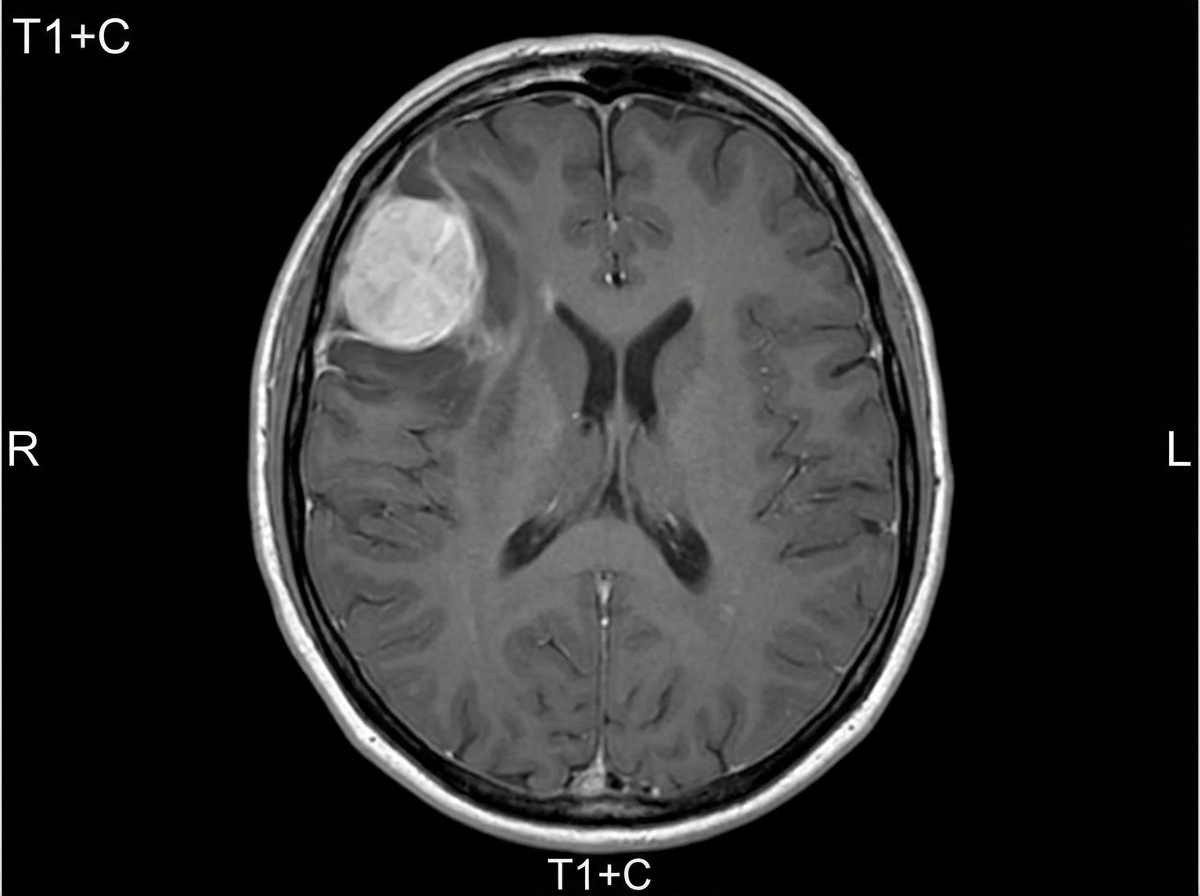

A 54-year-old woman comes to the physician because of paresthesias and weakness in her left leg for one year. Her symptoms have become progressively worse during this period and have led to some difficulty walking for the past month. She has had frequent headaches for the past 4 months. She has a history of hypertension and hypothyroidism. Current medications include amlodipine and levothyroxine. Her temperature is 37.3°C (99.1°F), pulse is 97/min, and blood pressure is 110/80 mm Hg. Neurologic examination shows decreased muscle strength in the left lower extremity. Deep tendon reflexes of the lower extremity are 4+ on the left and 2+ on the right side. The remainder of the examination shows no abnormalities. A complete blood count and serum concentrations of electrolytes, glucose, creatinine, and calcium are within the reference ranges. An MRI of the brain is shown. Which of the following is the most appropriate next step in management?